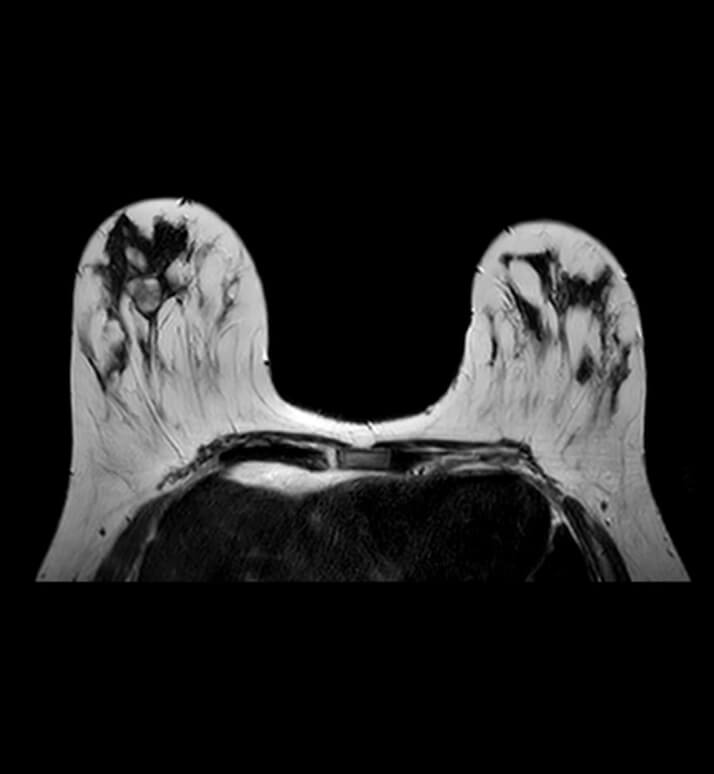

Women Imaging

Women's imaging in radiology is a specialized field of medical imaging that focuses on imaging the female reproductive system and breasts.